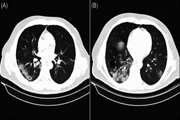

- توسعه و بهینهسازی پروتکلهای تصویربرداری ریه: برای تشخیص سریعتر و دقیقتر کووید-۱۹

- پیادهسازی فناوریهای هوش مصنوعی: برای تجزیه و تحلیل خودکار سیتی اسکن و کاهش زمان تشخیص

- انتشار مقالات تحقیقاتی با تأثیر بالا: در مورد روشهای تصویربرداری نوآورانه برای بیماران کووید-۱۹